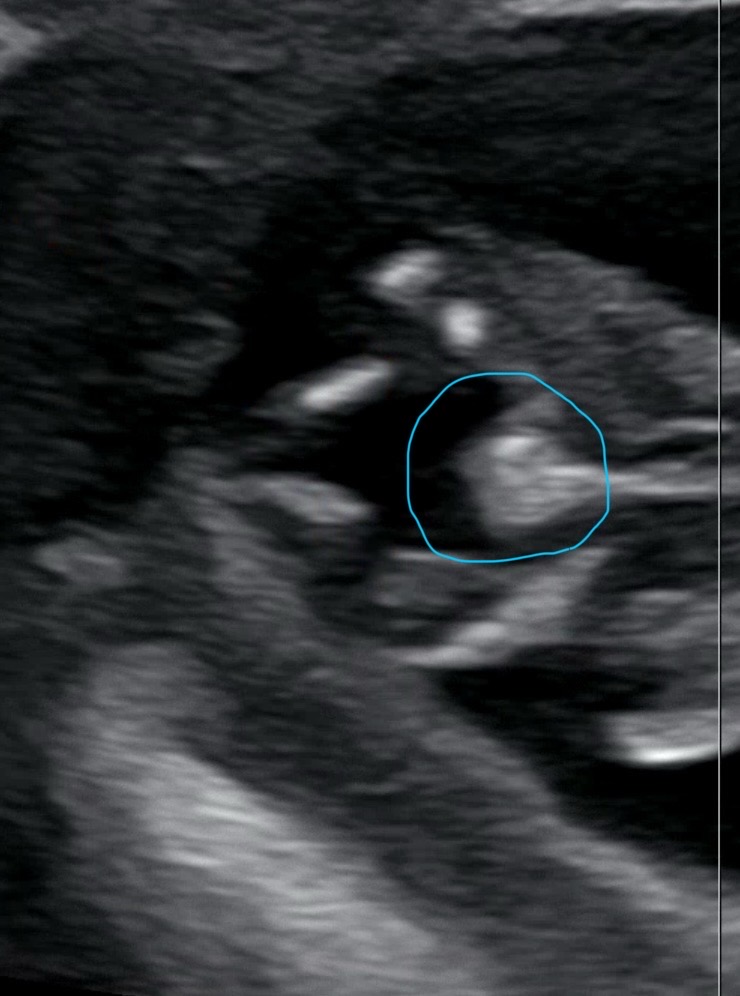

11주 2일에 초음파 사진인데요, 아무리 봐도 다리 사이에 뭔가 있어서요 ㅠㅠ 이 시기엔 다 나와있다고 하는데, 지인 보면 같은 주수에 저렇게 튀어나와 있지 않아서요.. 혹시 저렇게 보이는데도 딸인 분 계셨나요?

헙 .. 제 첫째가 딸인데 매끈했었어여.. 아들같아요!!! 저도 지금 둘째가 다리사이에 뭐거 있어서 넘 궁금한데 제 둘째 다리사이보다 뭔가 존재감이 뿜뿜인거같은데여?!☺️